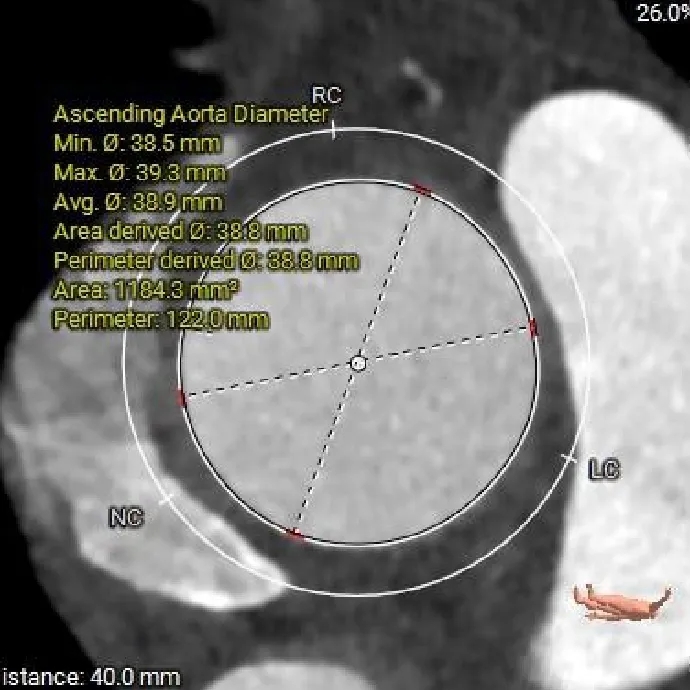

术前CT分析

主动脉根部测量

Annulus

26.6mm

LVOT

27mm

SOV

40.2*39.3*38mm

STJ

36.7mm

AAO

38.8mm

纯反流三叶瓣,瓣环内径26.6mm

流出道偏直筒型

瓣叶轻微增厚、无钙化

57°,近似横位心

瓣上结构测量

瓣上2mm

27.3mm

瓣上4mm

29mm

瓣上6mm

30.1mm

瓣上8mm

31.1mm

瓣上锚定空间逐渐增大,仅瓣上0-2mm可提供锚定力